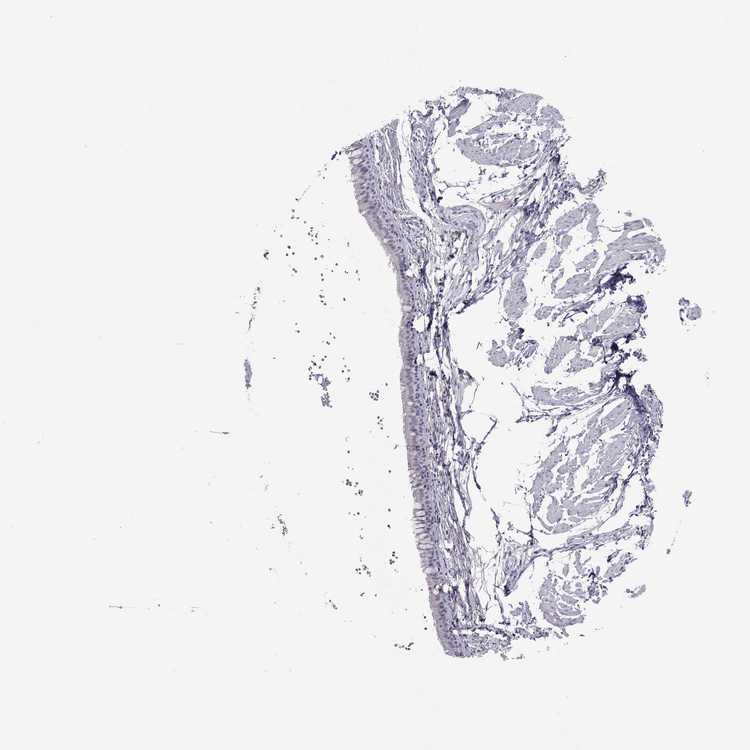

SOFT TISSUE 1 - Antibody stainingi

Antibody staining in the annotated cell types in the current human tissue is reported as not detected, low, medium, or high, based on conventional immunohistochemistry profiling in selected tissues. This score is based on the combination of the staining intensity and fraction of stained cells.

Each image is clickable and will lead to virtual microscopy that enables deeper exploration of all samples and also displays staining intensity scores, fraction scores and subcellular localization as well as patient and tissue information for each sample.

Antibody HPA074762Antibody CAB075684

Fibroblasts Not detectedNot detected

SOFT TISSUE 2 - Antibody stainingi

Peripheral nerve -Not detected